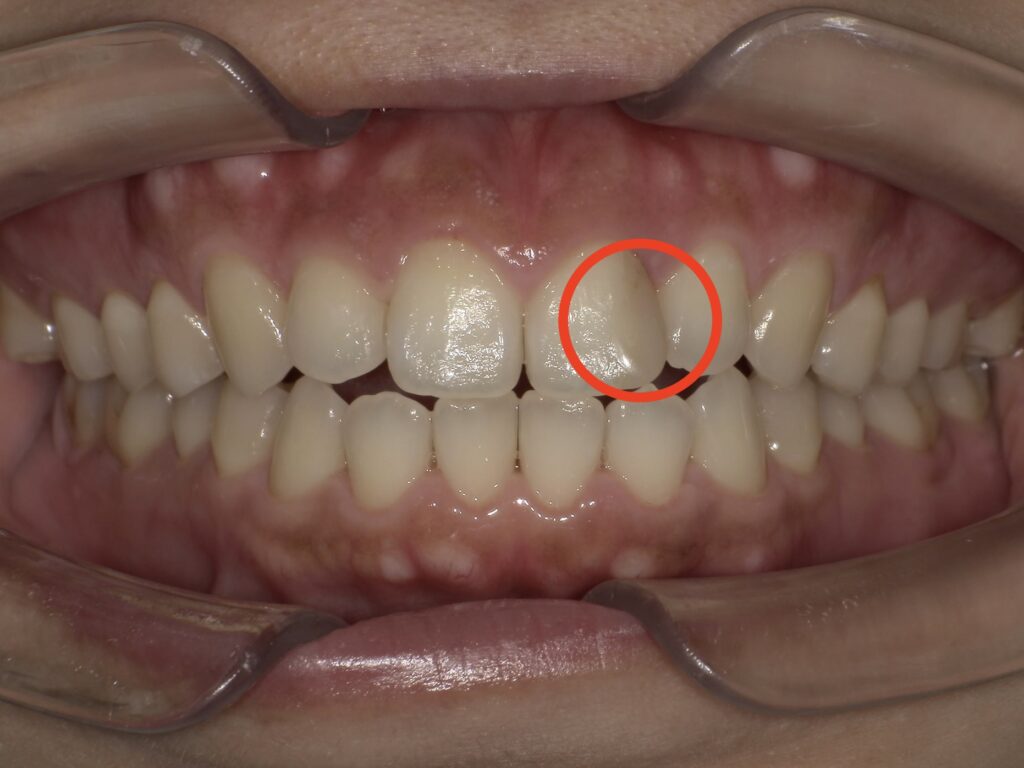

治療前後の写真です。

しみる症状もなく、希望通りの色まで白くすることができました。